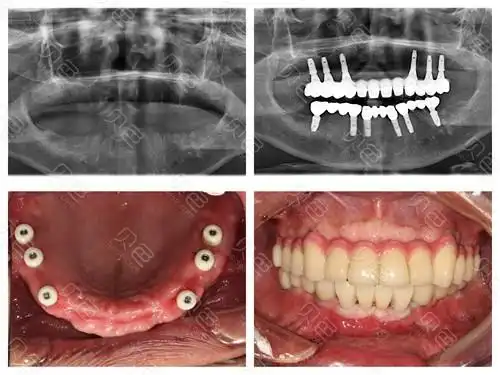

全口种植牙修复对比

全口种植牙前后对比效果图